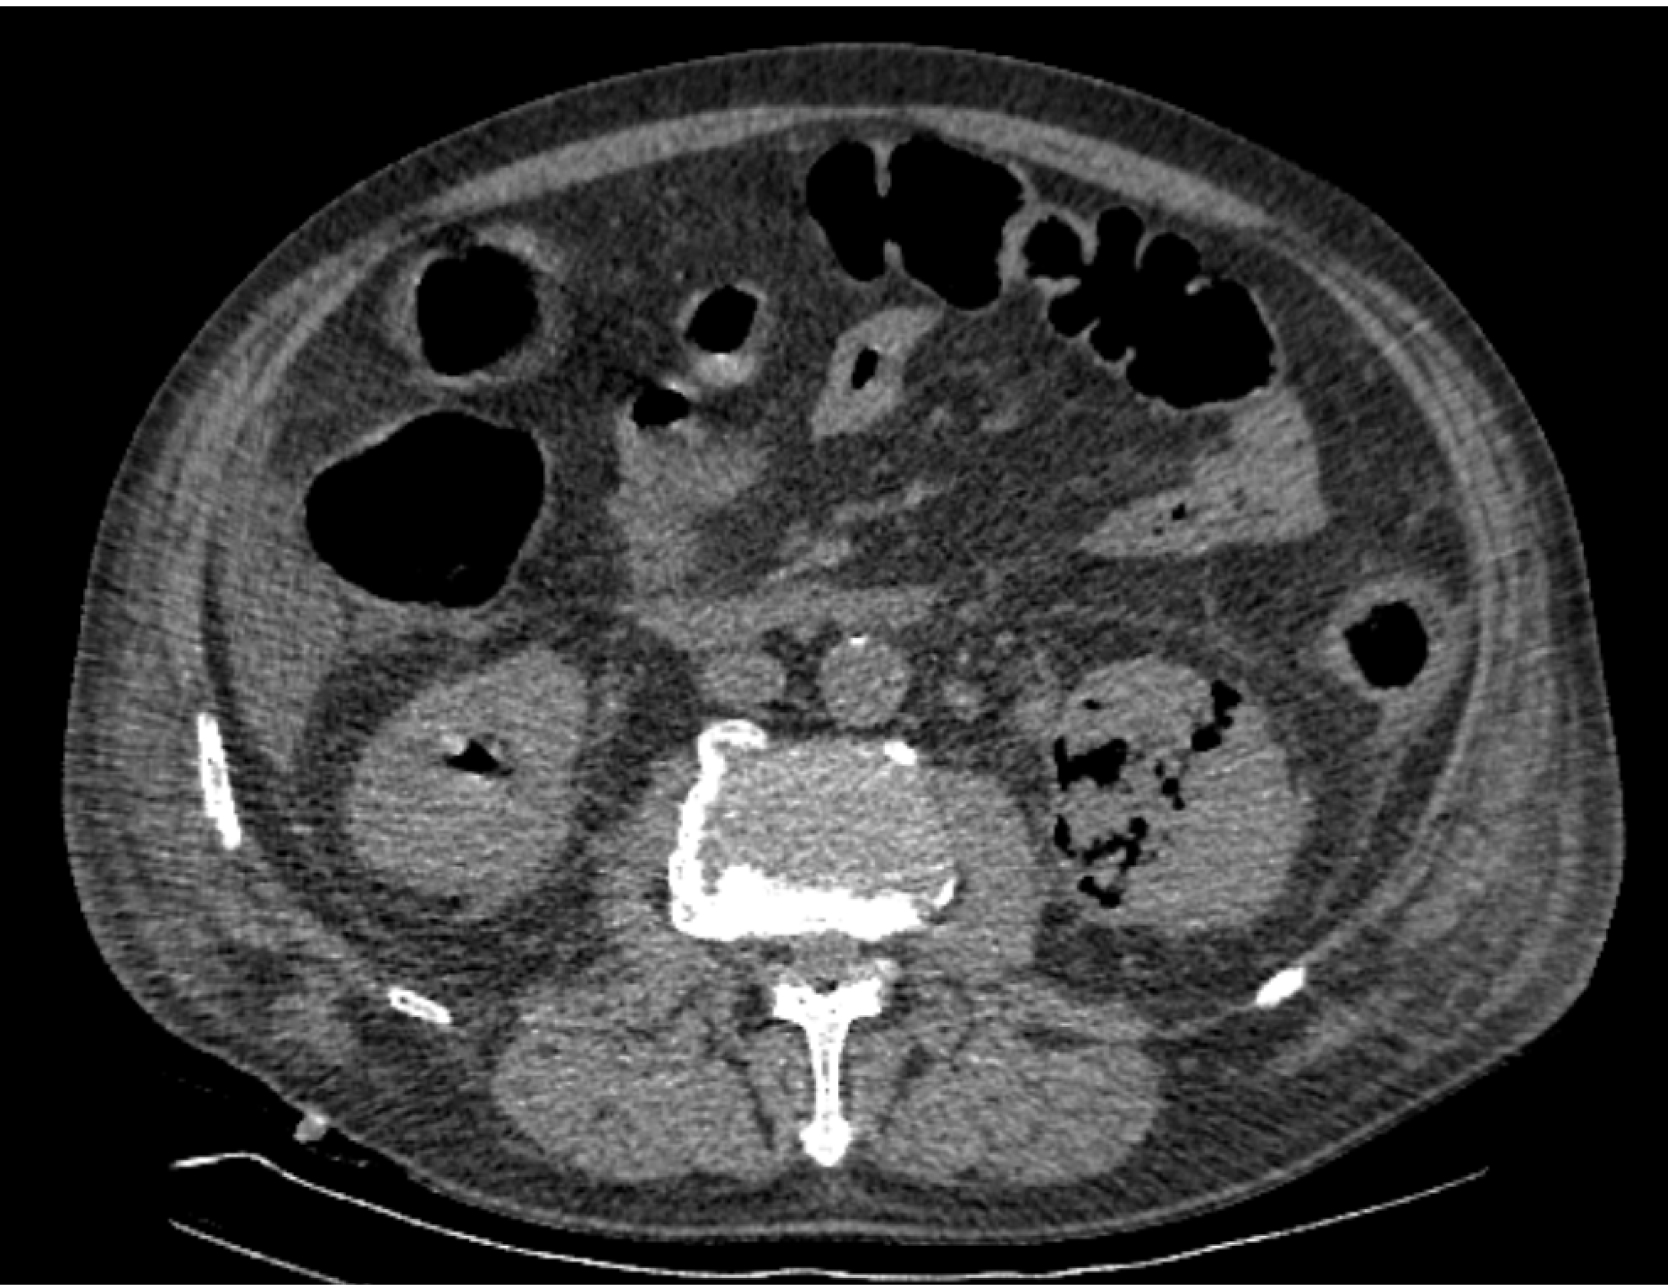

На следующий день состояние пациента оставалось тяжелым, с отрицательной динамикой, креатинин сыворотки возрос до 735,2 ммоль/л, Появились жалобы на слабость, тошноту. При осмотре: живот мягкий, вздут по всем отделам, при пальпации болезненный. Область почек не изменена, при пальпации безболезненна, патологических изменений в области почек не выявлено. Симптом поколачивания отрицательный билатерально. При УЗИ были обнаружены плевральный выпот по 300–400 мл с каждой стороны, гепатомегалия, увеличение размеров селезенки, асцит. Кроме того, в обеих почках были визуализированы тени, характерные для конкрементов. По данным компьютерной томографии (КТ) конкрементов не обнаружено, но в лоханке, на всем протяжении левого мочеточника и, частично, в правом мочеточнике, а также в мочевом пузыре визуализировался газ (рис. 1–6).

Рис. 3. Компьютерная томография органов брюшной полости, забрюшинного пространства, органов малого таза. Газ в левом мочеточнике